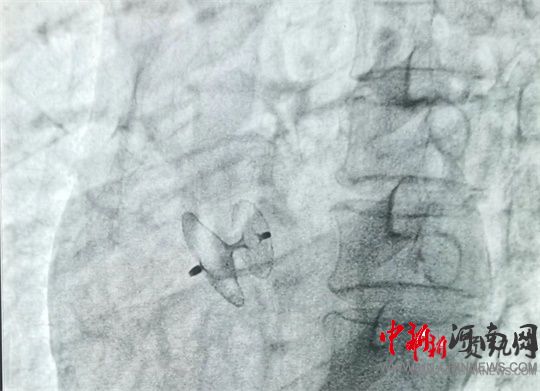

岳軍帶領(lǐng)團(tuán)隊(duì)將封堵器通過股靜脈送至卵圓孔處,展開封堵傘,使其與卵圓孔完美契合,成功封堵住缺口。經(jīng)床旁彩超證實(shí),無殘余分流,手術(shù)過程十分順利,全程僅用時(shí)60分鐘。術(shù)中及術(shù)后,患者均未出現(xiàn)不良反應(yīng),術(shù)后12小時(shí)即可下床活動(dòng)。